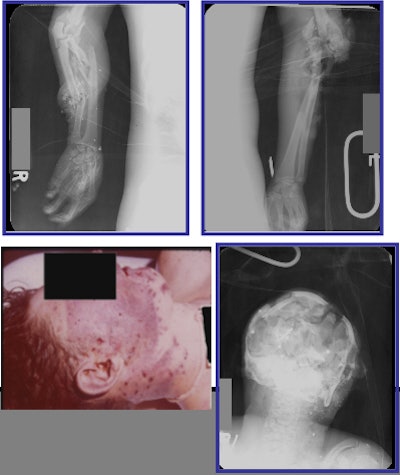

| An example of a pattern III mine injury. The three radiographs show a typical pattern III mine injury with injuries to both arms and extensive head injury. Caption courtesy of Drs. Justin Dodge and James Smirniotopoulos, photos and radiographs from the WDMET archive. |

- Pattern III results from handling a land mine. The victim sustains severe upper limb injuries with associated face injuries (Gray R., War Wounds: Basic Surgical Management, 1994, Vol.9, ICRC, Geneva).